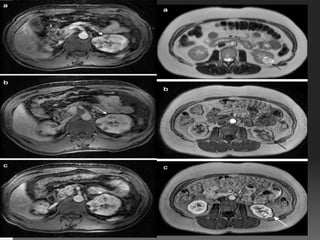

MRI OF GIT SECTIONAL ANATOMY

• #27 the most common fusion anomaly usually associated with accessory renal arteries easy to see the lower pole of both kidneys anterior to aorta on axial T2-weighted image

• #29 1-weighted gradient echo images before (a) and after (b) gadolinium administration. A mass in the renal pelvis (arrow) shows moderate enhancement after gadolin